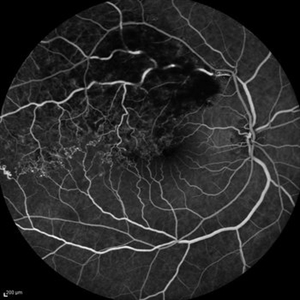

Behcet's Disease Behcet's DiseaseMar 13 2013 by Hamid Ahmadieh, MD Wide field FA of the right eye of a 23-year-old man with retinal vasculitis and branch retinal vein occlusion (BRVO) due to Behcet's disease . Photographer: Solmaz Shahmohammad, Negah Eye Center, Tehran Imaging device: Heidelberg Spectralis Condition/keywords: branch retinal vein occlusion (BRVO), retinal vasculitis